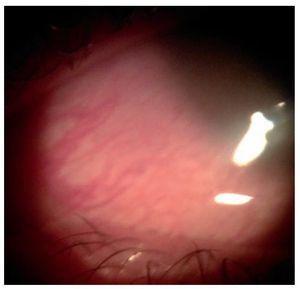

Female patient, 16 years old, without any significant medical or ophthalmological history. The patient went to the ophthalmology department in a private hospital in Monterrey, Mexico, 3 h after suffering an impact in the left eye caused by a flying insect. The patient was at school at the time of the accident and presented a sensation of a foreign body, redness, epiphora and burning in her left eye. Upon examination, the eyelids were found to be normal, the conjunctive was congested and the patient retained eye movement. In the biomicroscopy we observed transparent larvae moving over the bulbar conjunctive from the inferior towards the superior formix, as well as on the cornea. The larvae displayed a photophobic behavior since they moved away from the light from the slit lamp, thus impeding photography (figure 1). We applied an anesthetic chloridium (tetracaine) in order to perform their extraction with a swab, but it was difficult since they were strongly attached. We used tweezers to remove the 32 larvae; they were submitted to the microbiology department. We prescribed antibiotic therapy and anti-inflammatory medication (systemic and topical), and hospitalization. In addition, we prepared a tobacco solution made from 10 cigarettes diluted in 100 mL of distilled water mixed with eyewash lubricant and prescribed 2 drops every hour. There was no evidence of intraocular inflammation or inflammation of other organs in the eye. The right eye was normal. The patient remained hospitalized and was discharged on the third day given the fact she was no longer displaying symptoms. In her follow-up appointments 3 and 6 weeks after the event, she did not report any symptoms nor were abnormal signs found in the biomicroscopy.

Figure 1 Biomicroscopic photograph in which a non-pathognomonic conjunctival injection can be observed in the injury caused by the larvae, which presented photophobic behavior, which was why they could not be photographed.